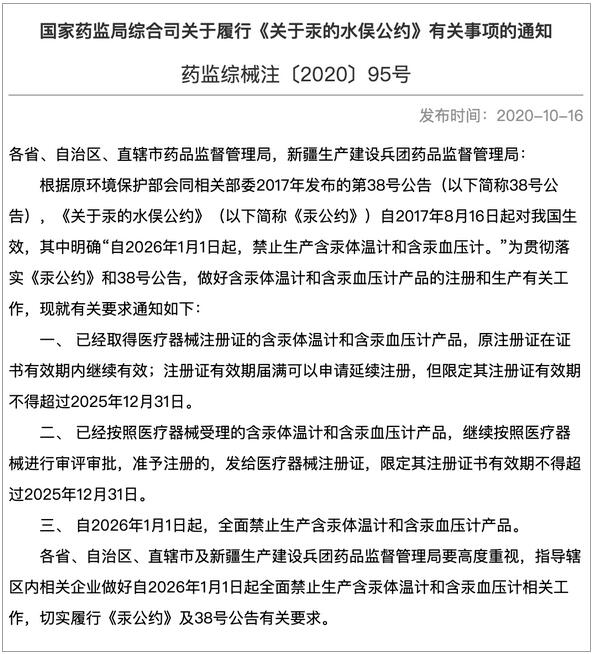

就在今天,國家藥監(jiān)局終于正式發(fā)布通知,明確指出:我國將于 2026 年1 月 1 日起,全面禁止生產(chǎn)含汞體溫計和含汞血壓計產(chǎn)品。

圖片來源:nmpa.gov.cn/